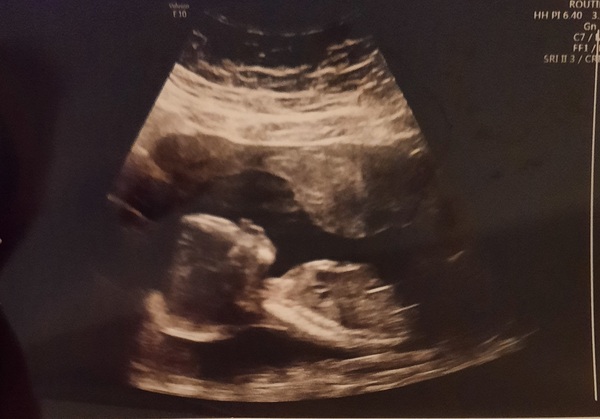

So I had a private scan tonight, my son is fine, very wriggly 💙🥰 All the measurements are great, he's actually a bit ahead again, approx. 17+2, but of course we're sticking to the official EDD which puts me at 17 weeks today. The most exciting moment of my life, I SAW HIS WILLY 🙃🤣 Brilliant! Posterior placenta also confirmed, the sonographer said she wouldn't be surprised at all if I felt the movements. Here he is, so big now 💙💙💙 xx

Ah lovely scan pic @PurplePansy05 - congratulations on your beautiful boy 💙💙💙💙💙 can you feel any kicking or movement?

Beautiful scan pic @PurplePansy05 😍

@Dia12 Thanks! No kicking, no, too early for this, but I occasionally feel some fluttering and it's a feeling as if a bubble was moving in my uterus if that makes sense. For days I've been wondering if that was him and I think it is, he moves A LOT 🤣 And with posterior placenta the sonographer said this sounds very familiar around this time.

Don't worry if yours is anterior though, it's completely normal to feel movements later then (she said it could be nearer 24 weeks, so appreciate that's a big difference) and they won't be as strong because you have an extra layer of protection then. When she showed me my placenta, they look so thick now, I was amazed. At 12 weeks there was barely anything there in comparison. WIth posterior I consistently read the description that babies "kick the crap out of mums" to the point of it becoming uncomfortable and painful later, so pros and cons of each I guess...and my DH played in our local football league when he was young, my son is already taking after him, so wish me luck for later 🤣

Thank you @MrsB2019x 🥰 He's a big boy, wriggly and making mummy gassy for the 4th month now, but he's my fav already, no doubt 💙😍😍😍 I just love how he stuck him bum cheeks out in full view of his willy for us to see, haha! 😄 There's no mistaking it if your baby decides to show it, ladies!

It's so strange when the sonographer scans you higher up close to the belly button and then all over the tummy, I've realised how much he's moved up and why my bump has popped out now. He moves from one side if the bump to another and she was following him, I was fascinated to watch so much going on and how she knew where he's moved 🙈 xx

@PurplePansy05 what a lovely photo, always such a good feeling to see them. And exciting to see proof that he's a boy!!